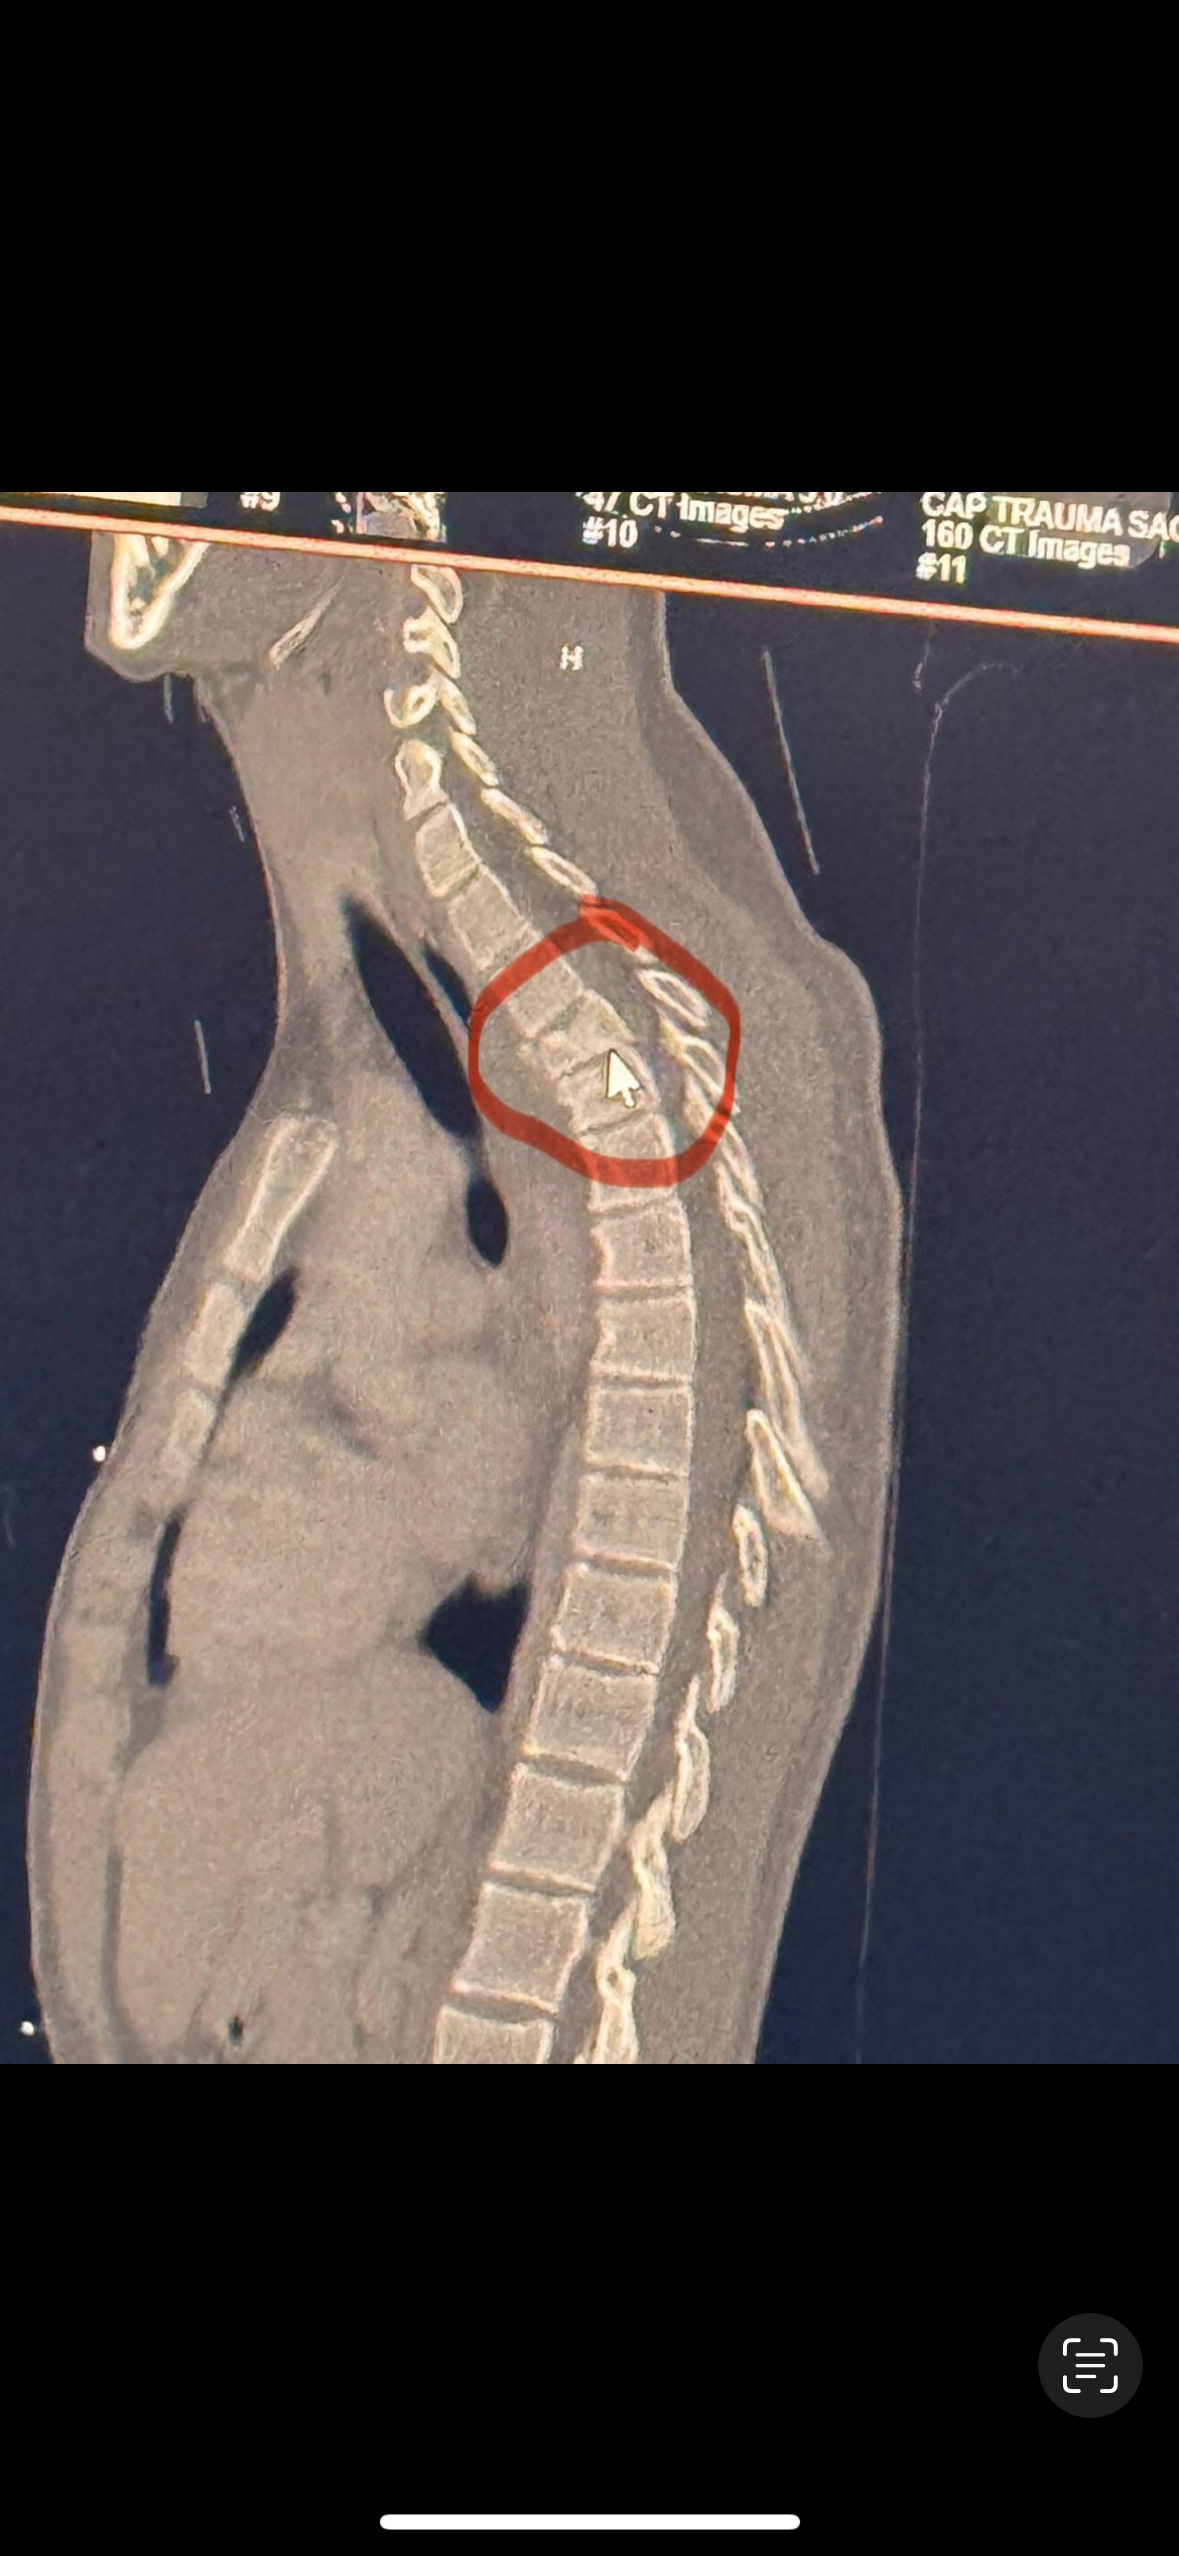

On July 5th, Brody was involved in a serious racing accident at Skagit Speedway in Washington State. During the event, he flipped his car and was rushed to Skagit Valley Hospital, where doctors confirmed a fractured back. He has since been transferred to Harborview Medical Center in Seattle, where he is undergoing spinal fusion surgery to repair the damage.

His 5 hour surgery was successful!

However he is in a lot of pain. The medical team has ordered a CT scan and we are awaiting his results.